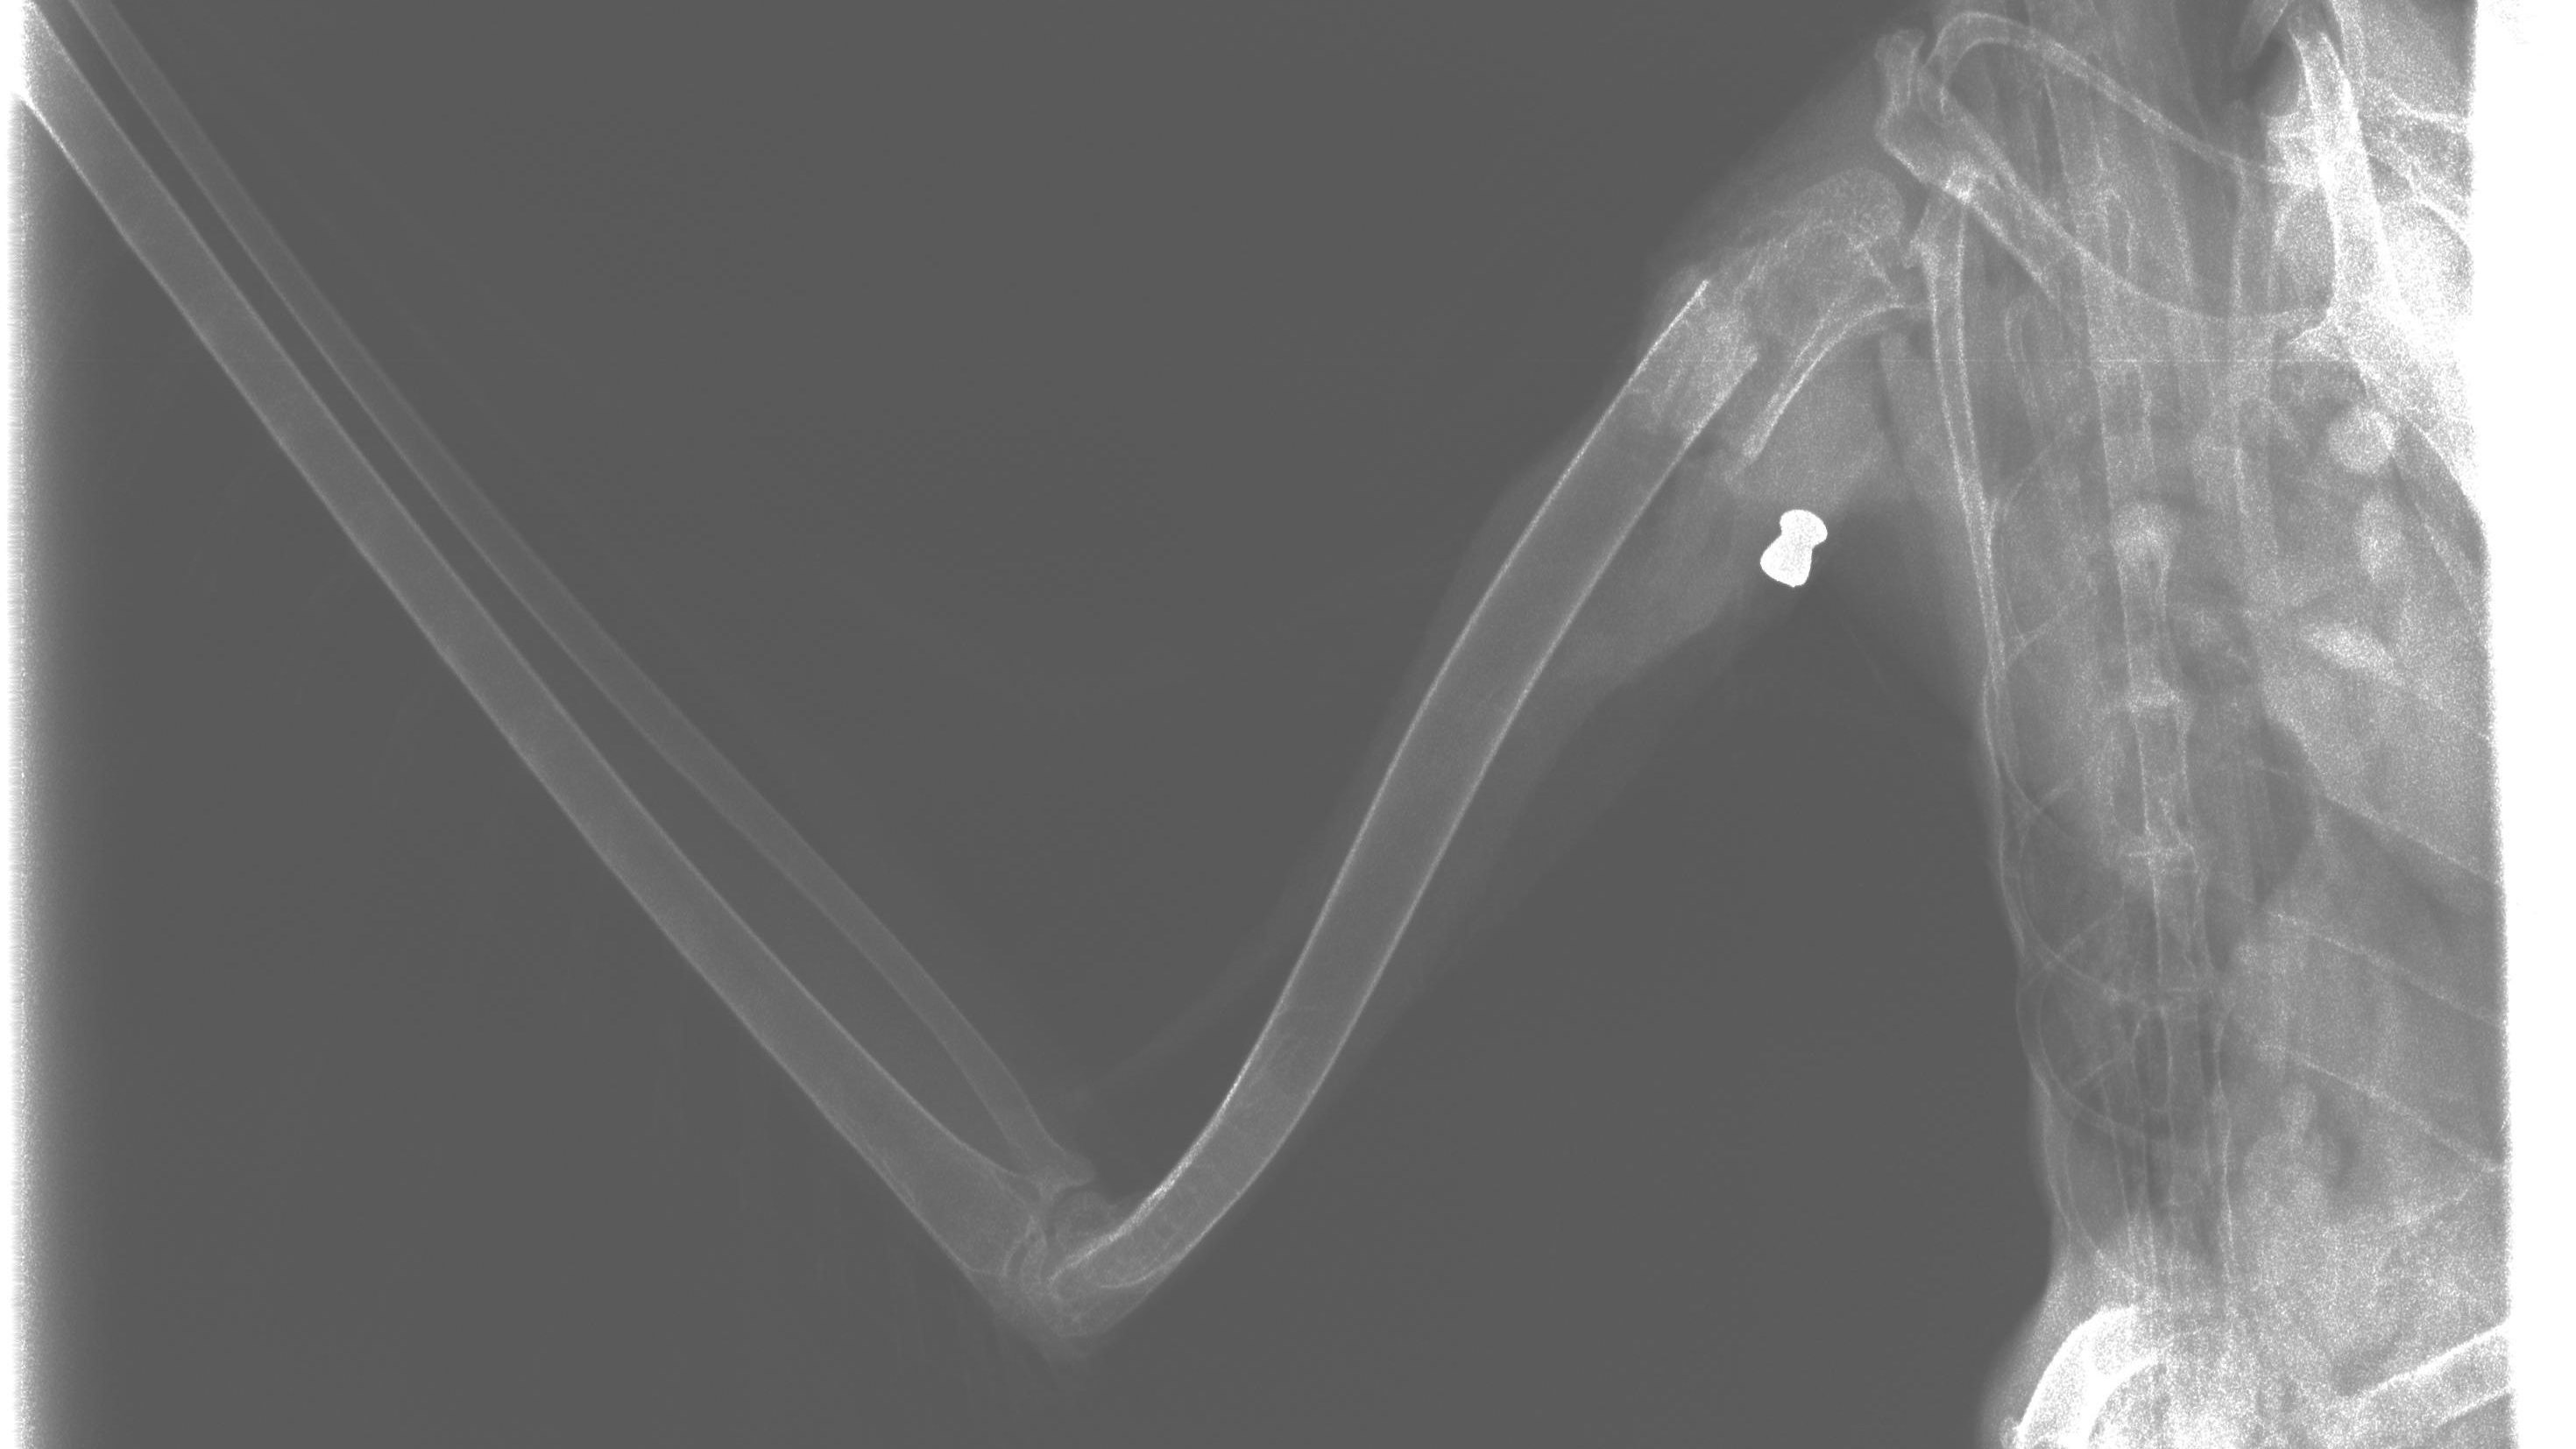

Ein Projektil steckte im Flügel des Graureihers